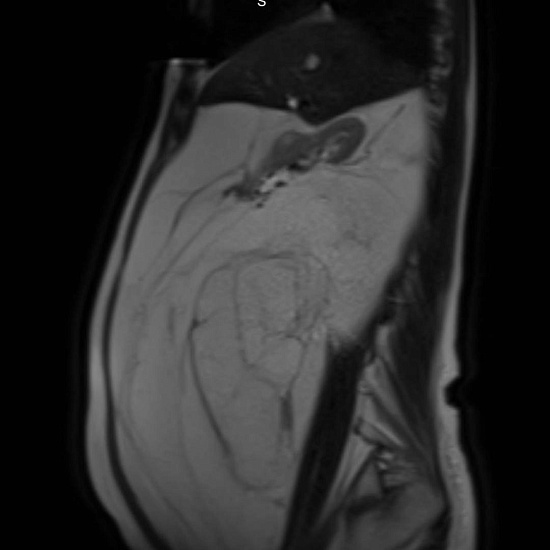

С целью оценки образования, а также уточнения расположения и взаимоотношения с органами брюшной полости проведено МРТ органов брюшной полости с внутривенным контрастированием.

При МРТ было выявлено жиросодержащее внеорганное объемное образование больших размеров с множественными неравномерными накапливающими контрастный препарат перегородками, занимающее большую часть брюшной полости с признаками смещения прилежащих внутренних органов.

Учитывая особенности структуры образования, распространенность и расположение, находка расценена как липосаркома (злокачественная опухоль жировой ткани).